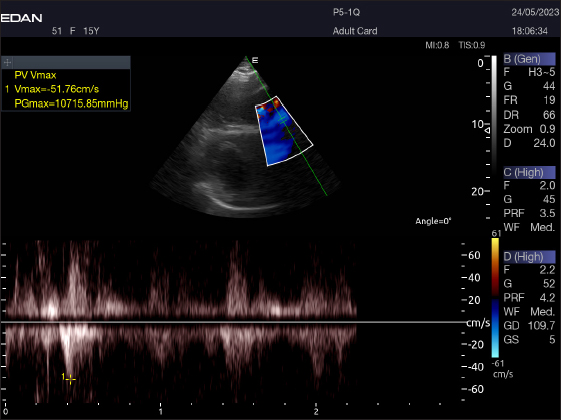

Right parasternal ultrasonography

There was difficulty in measuring the pulmonary valve from the right short parasternal view in most cases (58.4%) (Fig. 7).

Fig. 7. Right parasternal short axis of a 17-year racing she-camel showing pulsed wave Doppler of pulmonary valve.